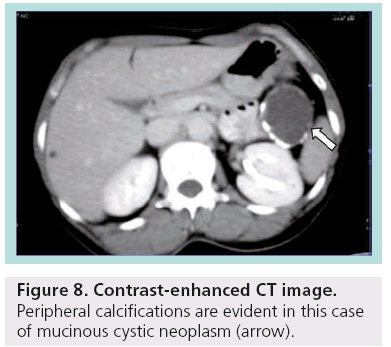

Despite advances and technological development in MDCT, differential diagnosis between serous and mucinous cystic lesions, which is the critical point for the proper management, is not feasible in many cases. There is significant variability in the CT appearance of serous and mucinous neoplasms of the pancreas, making CT an insensitive tool for differentiating these tumors. The dimension of the largest cyst (<2 cm in serous; >2 cm in mucinous) as well as the site of calcifications (central in serous; peripheral in mucinous) are the commonest criteria used (Figure 8) [14].